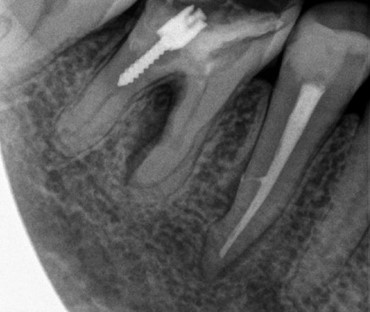

Как мы работаем с использованием микроскопа

На сегодняшний день использование микроскопа в стоматологической практике является неотъемлемым атрибутом в оказании качественного лечения, формирующим золотой стандарт оказания помощи...